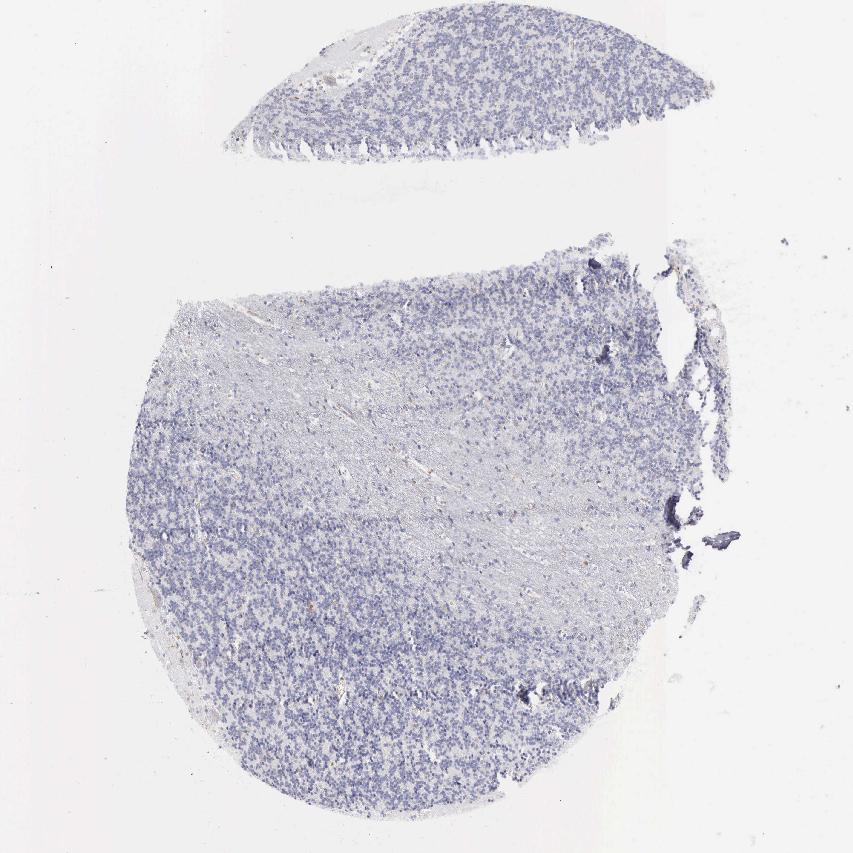

CEREBELLUM - Antibody stainingi

Antibody staining in the annotated cell types in the current human tissue is reported as not detected, low, medium, or high, based on conventional immunohistochemistry profiling in selected tissues. This score is based on the combination of the staining intensity and fraction of stained cells.

Each image is clickable and will lead to virtual microscopy that enables deeper exploration of all samples and also displays staining intensity scores, fraction scores and subcellular localization as well as patient and tissue information for each sample.

Antibody HPA002988Antibody CAB000460

Purkinje cells Not detectedNot detected

Cells in granular layer Not detectedNot detected

Cells in molecular layer Not detectedNot detected